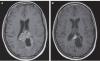

Если коротко, то это опухоль мозга, характеризующаяся своей абсолютной непредсказуемостью в виду огромного количества поломок генов. Их так много, что в рамках диагноза «глиобластома» выделяется еще минимум 6(!!!) молекулярных подвидов, как будто это все - разные заболевания!🙈 в глиобластомах есть мутации, которые встречаются при других опухолях, например, в раке лёгкого, кишке, меланоме и молочной железе. Учёные неплохо изучили и разработали на многие из этих мутаций свои таргетеые препараты, которые прекрасно работают при указанных заболеваниях и…. Совершенно, вообще никак не работают при глиобластоме. Как? А вот так. Потому что важен не только сам факт наличия известной поломки, но и множество других факторов, которые не могут быть учтены, к сожалению. Так вот, случай мужчины уникален тем, что после стандартного пути в виде операции —> лучевой терапии —> химиотерапии —> прогрессирования —> химиотерапии 2 линии —> прогрессирования ему дают «терапию отчаяния» и… получают полный ответ. Посмотрите фото в комментарии. Не надо быть диагностом, чтобы увидеть, что опухоль ушла. Чудо? Да не то слово!

@i_seme4ka_, более светлый участок практически с середине слева